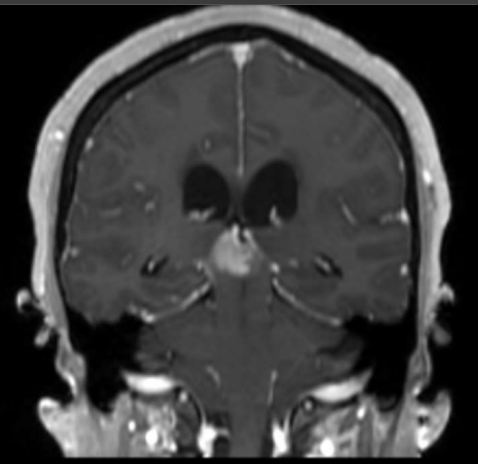

A 16-year-old presents with headaches, nausea, and blurred vision. His neurological examination is remarkable for impaired upgaze and convergence nystagmus. Contrast-enhanced MRI of the brain is shown (figure). Serum beta-HCG and alpha-fetoprotein levels are normal. What is the most likely diagnosis?

a. Endodermal sinus tumor

b. Embryonal carcinoma

c. Choriocarcinoma

d. Meningioma

e. Germinoma

Germinoma